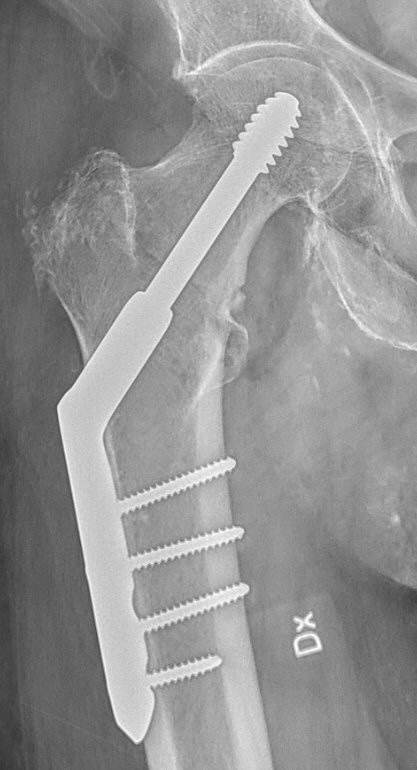

Operation: DHS-platta

DHS = Dynamic Hip Screw

- Kan användas vid många kollumfrakturer, pertrokantära och subtrokantära femurfrakturer.

- Används i praktiken mest vid basocervikala och stabila pertrokantära femurfrakturer.

- Det finns olika plattor med olika antal skruvhål, med eller utan LCP, med olika vinklar, med eller utan stabiliserande trokanterplatta och med glidskruv eller glidblad. Ofta väljs 4-hålsplatta utan LCP, utan trokanterplatta och med glidskruv.